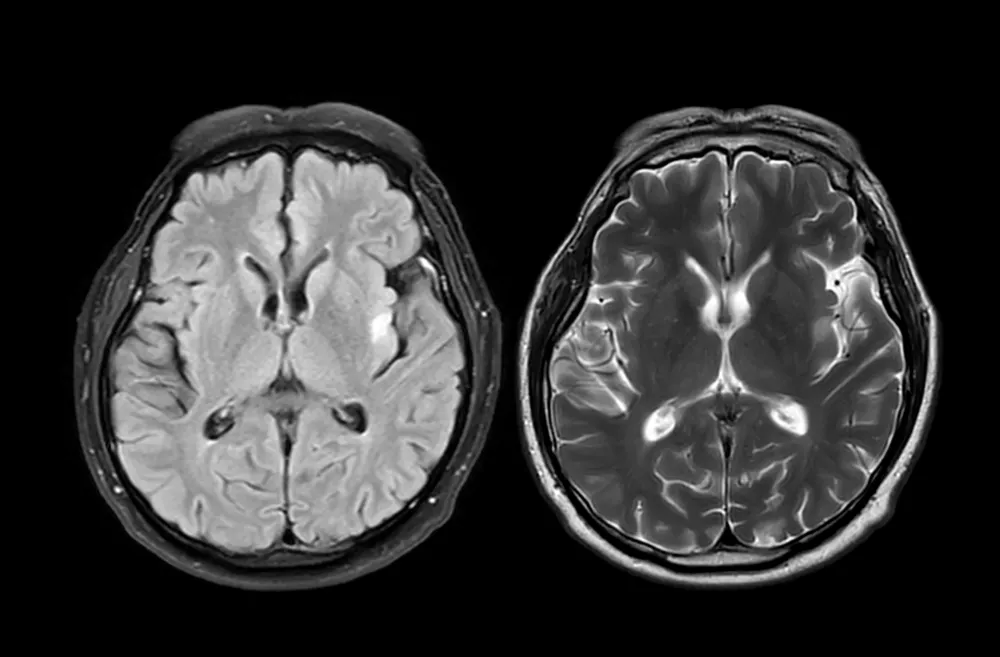

MRI brain scan axial T1W for detect Brain diseases sush as stroke disease, Brain tumors and Infections. / Foto: Mr.suphachai Praserdumrongchai